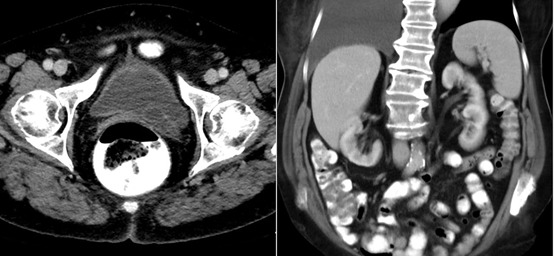

✳️التشخيص:

📌الفحص بالتصوير المقطعي المحوسب (CT)